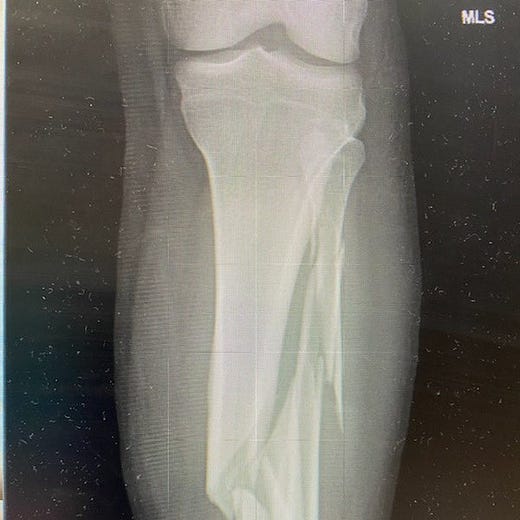

Everything after, rapid but in slow-motion. Does that make sense? Gingerly onto the sled, then the stretcher, then the Patrol-shack table. EMTs waiting. Amazing drugs incoming. Off, with scissors, my ski pants. Removing the boot, pain distilled. Not your knee – your leg. Broken bones. Did not penetrate the skin. Into the ambulance. Rumford Hospital: X-rays and more pain meds mainlined. A bed in the hallway. From the next room a woman, emphatic, that she don’t need no Covid vaccine in her body. All night there. The staff amazing. I would need surgery but there were no surgeons available until the next day. A room opened and they wheeled me in. In a druggy haze they splinted my leg. A train of drunks and incoherents as the bars emptied out. Sleep impossible.

The next morning a long ambulance ride to Central Maine Medical in Lewiston. There a surgeon, a skier himself, amazed by my break – tibia and fibula. “Spectacular,” he called it. “You have strong bones. They resisted the break. When they broke, they exploded.” A spiral fracture splintering into what he called butterfly fragments. “Normally those are three or four millimeters long. Yours were 20. Just amazing.”

Surgery happened in an instant. At least for me, drugged and grateful to be a citizen of the future, of this amazing century with this impossible technology. Here is what he fixed: